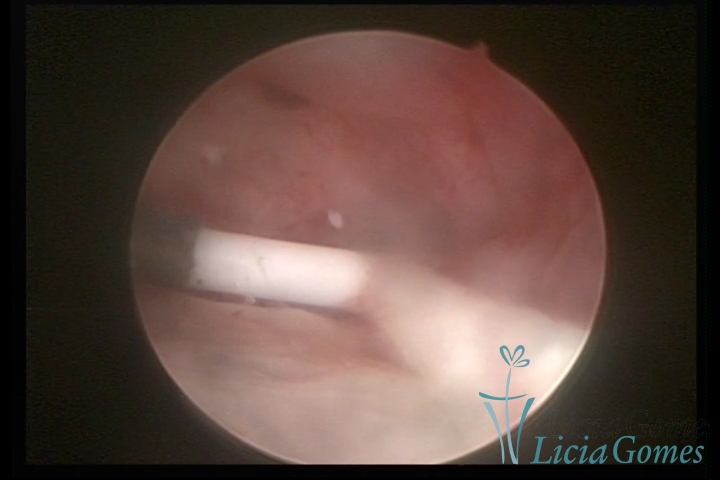

Cervical canal with IUD string